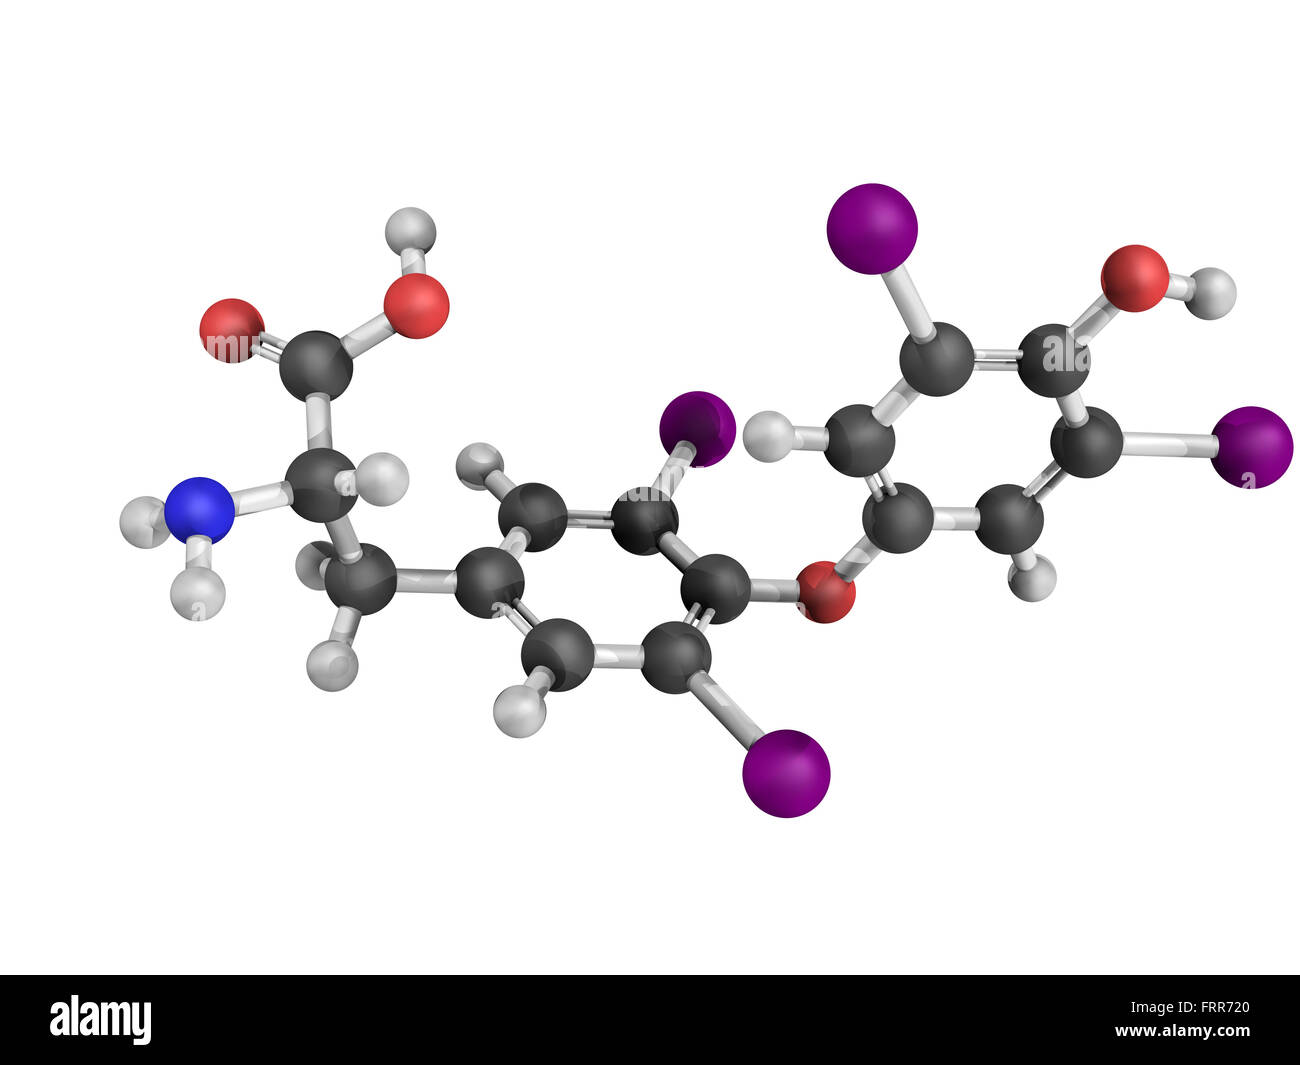

RFFRR720–La thyroxine hormone thyroïdienne molécule. Thyroxine est une hormone thyroïdienne qui joue un rôle dans le métabolisme de l'énergie règlement